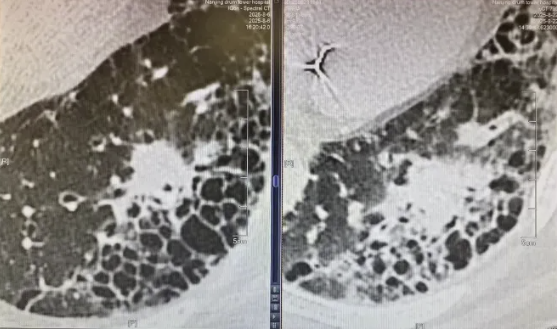

本次观摩学习了2例肺癌患者介入手术全程。第一例是79岁老年患者,该患者有肝癌,右侧肺鳞癌手术史,本次再发结节,不能再次手术,进行了磁导航支气管镜下机器人辅助活检及射频消融治疗。

第二例为81岁合并有肺纤维化的老年患者,由于肺功能较差,不能耐受手术,进行了磁导航下支气管镜肺活检以及冷冻消融。